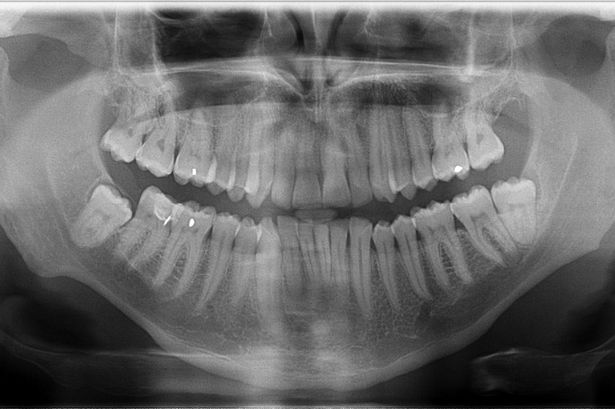

As mentioned above, it is hard (any potentially undesirable) to directly build a GDP from biomedical images. We hence learned the prior from natural-scene images, but validate it here on biomedical images. We first show stability of the present GDP for biomedical images. For this, we collected a small dataset of biomedical images, including X-ray, MRI, electron microscopy, and fluorescence microscopy images. Some examples are shown in Figs. 10 and 24.

We compute the RMS distance from the GDP for each image’s gradient distribution. The distance histogram is shown in Fig. 11. This confirms that most gradient distributions are close to the GDP learned from natural-scene images. As expected, the range of RMS for this test set of biomedical images is larger than the range of RMS for the training set of natural-scene images.